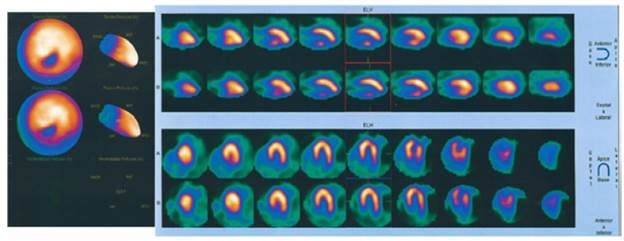

This paper reports the case of 52-year-old male patient, from Bogotá D.C., without ethnicity, and architect for profession. He presented with a history of dyslipidemia, and consulted due to a 6-month history of episodes of sharp retrosternal chest pain that radiated to the back and neck, lasting less than 5 minutes, associated with moderate efforts and attenuation at rest. He also showed progressive deterioration of his functional class. Physical examination was normal and electrocardiogram showed sinus rhythm with a heart rate of 70 bpm, with changes compatible with necrosis in the lower and lateral sides. Transthoracic echocardiogram showed left ventricular ejection fraction of 58%, with segmental alterations in contractility due to severe hypokinesis in the apical lateral, apical infarction and concentric remodeling of the left ventricle with a non-mobile image of an 11x9mm calcium refringence suggestive of a small organized thrombus. For this reason, a myocardial perfusion with pharmacological stress (dipyridamole) was performed, which was negative for myocardial ischemia, with lower wall necrosis in the middle and distal segments. Figure 1 shows a severe perfusion defect in the middle and distal segments of the inferior wall, not reversible, and with mild hypokinesia; the estimated area of necrosis is 5-7% of the total myocardial mass.